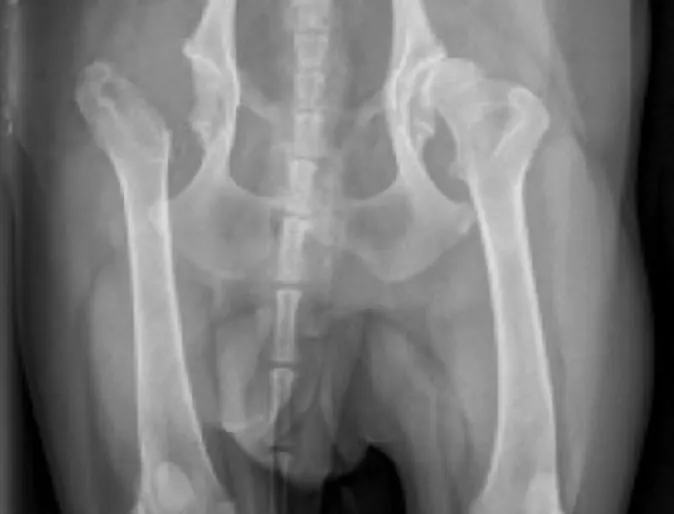

Canine Hip Dysplasia

Canine Hip Dysplasia (CHD) is a developmental disorder of the hip that begins withjoint laxity and progresses to arthritis over a period of several months to years